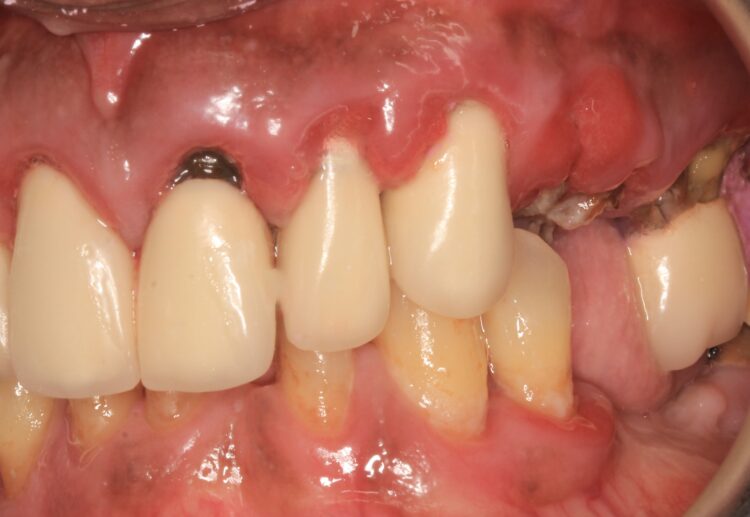

A 60-year-old male patient presented with major concerns about unsatisfactory smile appearance, limited masticatory function and pain while chewing. The patient was in good general health. The clinical and radiographic examination revealed failing ceramic restorations, rampant caries, non-restorable teeth, soft tissue inflammation, residual roots and missing teeth. Comprehensive digital records, including extraoral and intraoral clinical photographs, were collected as part of the initial assessment. The case was deemed suitable for full arch implant-retained restoration using advanced techniques.

Ensuring the clinician is prepared for these risks, and they have been adequately communicated with the patient, treatment can be highly successful with diligent planning and patient compliance with excellent oral hygiene. This patient underwent extensive courses of hygiene to improve the health of the periodontal tissues and was motivated to improve his cleaning routine.

The plan was followed meticulously on the day of surgery. The canines, left and right premolars and a right molar were used to support the surgical guide together with three bone anchor pins. Following the digital plan, all other teeth were extracted and thorough degranulation of the sockets was performed. No bone reduction was performed for both the provisional and final prosthesis in accordance with the Misch classification for an FP1 approach.[iv]